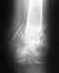

На мой взгляд, представленный план неоптимален, и может создать больше проблем, чем решить.

Стержень тонкий, на уровне нижнего перелома нестабильность, в этих условихя пластику делать бесперспективно - из-за подвижности не прорастут сосуды, соответственно, не приживет трансплантат.

И при закрытом интрамедуллярном остеосинтезе вообще пластики делать ни к чему. Здесь нужно убрать этот гвоздь, рассверлить канал и ввести гвоздь больше диаметром. И заереть его внизу понадежнее, винтами большего диаметра и не короткими, как сейчас. Вверху - динамически и с компрессией. Тут же можно будет ходить без ограничения нагрузки.